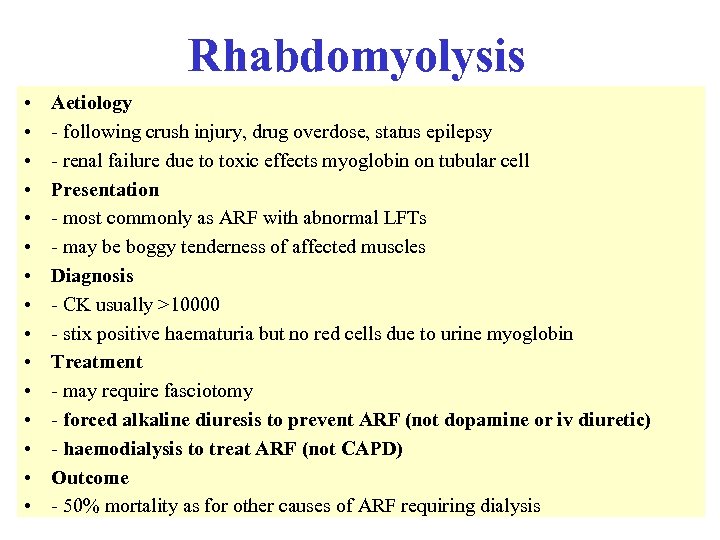

Reflux nephropathy • Treatment • - RCTs have shown equal efficacy of continuous antibiotics until puberty and ureteric reimplantation in children with reflux and UTI - reimplantation now less common than before • - prophylactic antibiotics for asymptomatic infection now no longer recommended after puberty • - only patients with serious recurrent UTI or pyonephrosis require nephrectomy before transplantation (bilateral nephrectomy not routine) • Outcome • - combination of reflux and UTI usually required to cause scarring and CRF • - but new scars rarely develop after 8 yrs of age • - progressive loss of renal function, invariably assoc with HT and proteinuria, can occur in absence of both UTI and reflux if GFR<50 ml/min • - CRF not caused by recurrent acute pyelonephritis - UTI present in a minority of adults • - accounts for ~ 20% cases ESRD requiring dialysis (not 50%)

Reflux nephropathy • Treatment • - RCTs have shown equal efficacy of continuous antibiotics until puberty and ureteric reimplantation in children with reflux and UTI - reimplantation now less common than before • - prophylactic antibiotics for asymptomatic infection now no longer recommended after puberty • - only patients with serious recurrent UTI or pyonephrosis require nephrectomy before transplantation (bilateral nephrectomy not routine) • Outcome • - combination of reflux and UTI usually required to cause scarring and CRF • - but new scars rarely develop after 8 yrs of age • - progressive loss of renal function, invariably assoc with HT and proteinuria, can occur in absence of both UTI and reflux if GFR<50 ml/min • - CRF not caused by recurrent acute pyelonephritis - UTI present in a minority of adults • - accounts for ~ 20% cases ESRD requiring dialysis (not 50%)

18 With regard to lupus nephritis: • A It may present with a rapidly progressive glomerulonephritis • B It may present with histological changes similar to diabetic nephropathy • C It should be treated with oral steroids alone when associated with a membranous histology • D It should only be treated with cytotoxic agents when serum creatinine > 120 mol/l • E Frequently complicates drug induced SLE

18 With regard to lupus nephritis: • A It may present with a rapidly progressive glomerulonephritis • B It may present with histological changes similar to diabetic nephropathy • C It should be treated with oral steroids alone when associated with a membranous histology • D It should only be treated with cytotoxic agents when serum creatinine > 120 mol/l • E Frequently complicates drug induced SLE

18 With regard to lupus nephritis: • A It may present with a rapidly progressive glomerulonephritis • B It may present with histological changes similar to diabetic nephropathy • C It should be treated with oral steroids alone when associated with a membranous histology • D It should only be treated with cytotoxic agents when serum creatinine > 120 mol/l • E Frequently complicates drug induced SLE

18 With regard to lupus nephritis: • A It may present with a rapidly progressive glomerulonephritis • B It may present with histological changes similar to diabetic nephropathy • C It should be treated with oral steroids alone when associated with a membranous histology • D It should only be treated with cytotoxic agents when serum creatinine > 120 mol/l • E Frequently complicates drug induced SLE